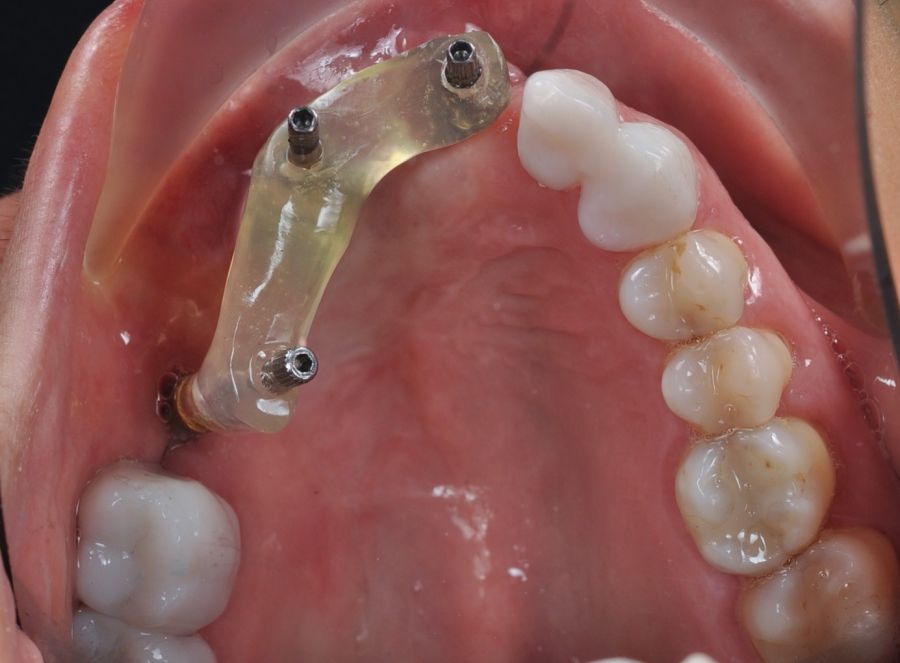

Una vez finalizada la radioterapia, la paciente se encontraba libre de enfermedad. Por lo que se procedió a la restauración definitiva implantosoportada. Tras la segunda fase, se colocaron dos pilares transepiteliales Multiunit Ò rectos y un pilar Multunit Ò angulado de 17º (Figura 10).

Para la fabricación de las estructuras, se eligió el óxido de zirconio monolítico como material restaurador sobre interfases metálicas en el puente implantosoportado, y coronas de óxido de zirconio monolítico en los dientes tallados previamente (1.7, 1.6, 2.2 y 2.3). Se tomaron impresiones de cubeta abierta con silicona de adición pesada y fluida (Zhermack Elite HD, Gmbh). Se realizó una prueba de pasividad analógica y el resto del proceso se confeccionó de manera digital, por lo que se hicieron pruebas estéticas de dientes impresas en 3D sobre interfases metálicas, para hacer todos los ajustes de función y estética previos al fresado del zirconio monolítico (Figuras 11, 12 y 13).

Finalizado el tratamiento oncológico y confirmada la ausencia de enfermedad activa, se procedió a la segunda fase quirúrgica con la colocación de pilares transepiteliales Multiunit®. La integración de los implantes cigomáticos y del implante endoóseo fue satisfactoria, observándose estabilidad clínica y ausencia de signos de periimplantitis.